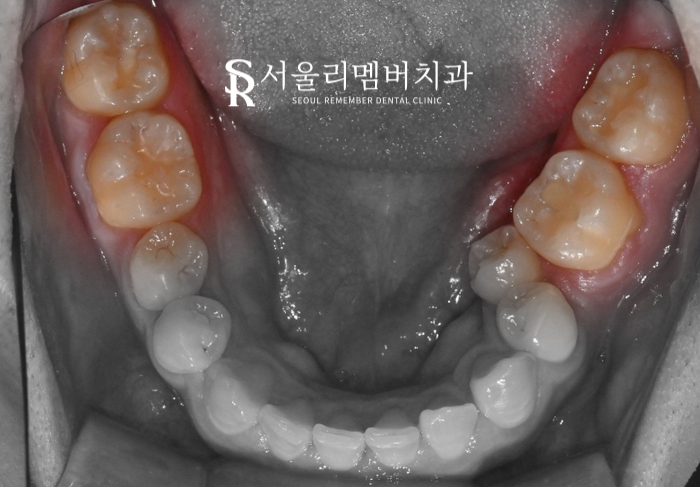

감염된 곳을 제거 하니 신경과 가깝기는 하나

다행히 치수가 드러나지는 않아

진정시키는 재료를 넣고

그 위에 레진 치료를 완료 하였습니다.

어디를 치료 했는지 모를 정도로

자연스럽게 마무리 되었습니다.